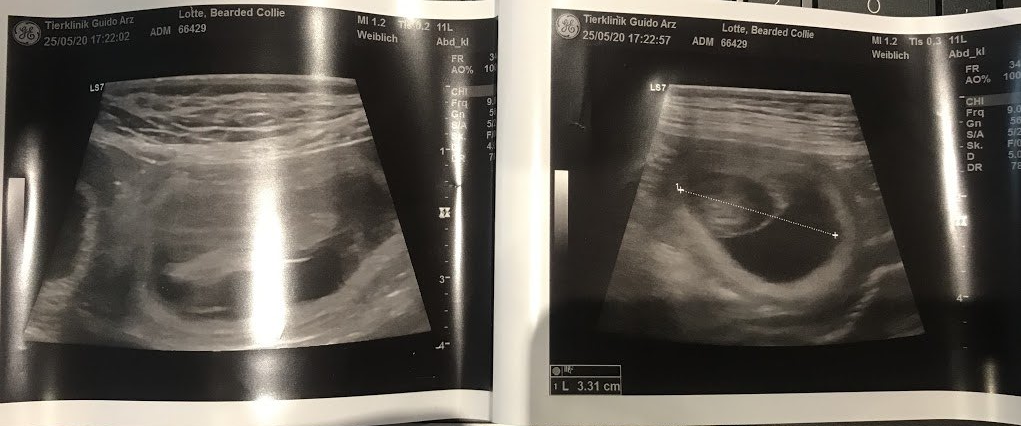

The ultrasound confirmed it.....Lotte is expecting babies and we are overjoyed again.